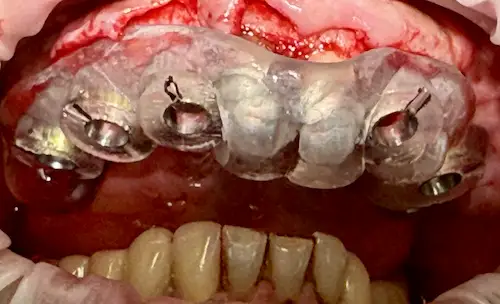

All-on-4 ® – Patientenfall

Bei Zahnlosigkeit oder nicht mehr erhaltungswürdigen Zähnen wünschen sich die Patient*innen der Praxisklinik Herne natürlich zeitnahe und minimalinvasive Lösungen. Dank des All-on-4 ® / All-on-6 ®–Konzepte können wir ihnen diesen Wunsch oftmals innerhalb nur eines einzigen Behandlungstages erfüllen: 4 bzw. 6 Zahnimplantate werden gesetzt und bilden im Folgenden die Grundlage für den passenden festsitzenden oder herausnehmbaren Zahnersatz. Die einzelnen Behandlungsschritte veranschaulichen wir Ihnen anhand eines aktuellen Patientenfalls aus diesem Jahr.

Der Patientenfall

Unser 55-jähriger Patient stellte sich uns nach Jahrzehnten der Nichtbehandlung mit einen stark kariösen und nur zum Teil bezahnten Kiefer vor. Aufgrund einiger abgebrochener Zahnwurzeln wurde schnell ersichtlich: Der bisherige Zahnersatz kann nicht erneuert werden; außerdem wünschte sich unser Patient in Zukunft einen gaumenfreien festsitzenden Zahnersatz. Alles deutete Richtung All-on-4 ® / All-on-6 ®–Konzept.

Der chirurgische Eingriff im Detail

Der Tag der Operation ist gekommen: Im ersten Schritt werden die noch vorhandenen Zähne gezogen sowie die Wurzeln und vereinzelte Zysten restlos entfernt. Dies erwies sich im vorliegenden Fall als extrem komplex und folgenreich: Beim Extrahieren gingen Teile der Knochenwände verloren, was einen deutlichen Mehraufwand beim Aufbau des Kieferkamms nach sich zog. Zuzüglich zu Knochenersatzmaterial verwendete Dr. Mintert dafür 2 Collagen Blöcke, 2 Membranen und 0,3 ml Emdogain. Letzteres dient der Entwicklung von zahnstützendem Gewebe. Auch Eigenknochen aus einem zweiten OP-Gebiet kam zum Einsatz. Im Oberkiefer wurde außerdem ein sogenannter Sinuslift durchgeführt, der – vereinfacht gesprochen – die Kieferhöhlen anheben soll. Nun waren die Grundlagen für den nächsten Schritt geschaffen: Eine eigens angefertigte Bohrschablone ermöglicht die navigierte Implantation. So fanden alle acht Implantate trotz ungeplanter Komplikationen ihren rechten Platz im Mundraum. Abschließend wird L-PRF Plasma, d.h. zentrifugiertes Eigenblut eingebracht, um die Wundheilung zu unterstützen. Als Zahnersatz werden zwei festsitzende Keramikbrücken gewählt und auf künstliche Keramikaufbauten geklebt. Diese wiederum sind mit jeweils vier Implantaten verschraubt.